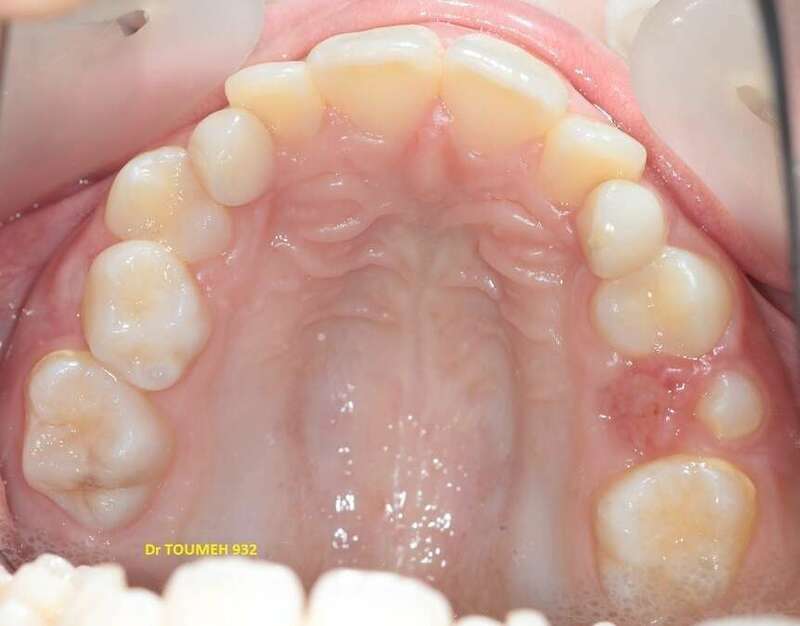

Avant

Après